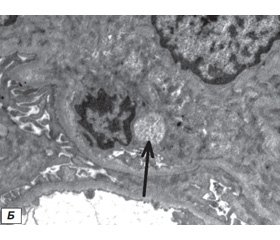

Электронно-микроскопическое исследование нефробиоптата. С целью изучения роли герпесвирусов в развитии ГП методом ультраструктурного анализа исследованы нефробиоптаты пациентов с ГП, у которых методом ПЦР в крови или ткани почек была обнаружена ДНК вирусов семейства Herpesviridae. Наличие этиологического агента с выявлением вирусных частиц, находящихся на ранних и конечных стадиях морфогенеза, было подтверждено только в одном из исследованных биоптатов. Чаще отмечались косвенные признаки инфекции. В клубочках визуализировались как специфические, так и неспецифические дистрофические изменения подоцитов. Кариоплазма в центральной части ядра была светлой, хроматин располагался вдоль внутреннего слоя ядерной мембраны. В дистрофически измененных клетках отмечалось исчезновение ядрышек, пери- и межхроматиновых гранул и накопление беспорядочно расположенных глыбок хроматина. Другой тип изменений наблюдался в цитоплазме инфицированных клеток. Специфические дистрофические процессы проявлялись в виде резких расширений канальцев и цистерн эндоплазматического ретикулума c накоплением электронно-плотных включений внутри. Обнаруживались светлые «пустые» вирусные частицы размером 80–90 нм и отдельные ДНК-содержащие нуклеокапсиды. Большинство вирусных капсидов содержали электронно-плотную сердцевину, что свидетельствовало о репродуктивном типе инфекционного процесса с формированием зрелых вирусных частиц (рис. 1).

Анализируя результаты ультраструктурного анализа, можно сделать вывод, что герпесвирусы оказывают влияние на развитие и течение патологического процесса в почечной ткани и могут являться этиологическими факторами в патогенезе и прогрессировании ГП. Данные ультраструктурного состояния подоцитов важны для дифференциальной диагностики и последующего выбора тактики патогенетической терапии ГП.

Показано, что обнаруженные в биологическом материале специфические фрагменты НК герпесвирусов указывают на роль в поражении гемотканевого барьера, повреждении эндотелиоцитов, перицитов, подоцитов в зонах клубочкового аппарата. В результате ультраструктурного анализа пункционных биоптатов почки детей с гломерулопатиями, у которых методом ПЦР в крови или ткани почек была обнаружена ДНК вирусов семейства Herpesviridae, в цитоплазме подоцитов верифицировано наличие капсидов вируса герпеса. Полученные данные свидетельствуют, что герпесвирусы оказывают влияние на развитие и течение патологического процесса в почечной ткани и могут являться триггерами в патогенезе и прогрессировании гломерулопатий.